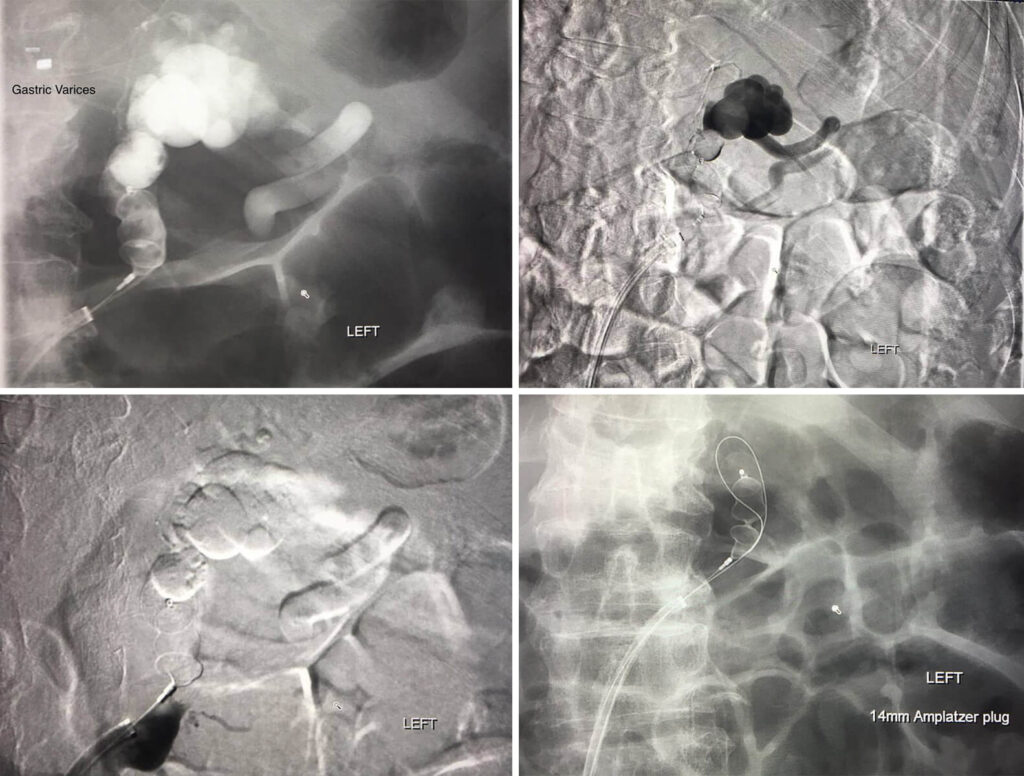

Plug assisted Retrograde Transveonous Obliteration of the Gastric Varices.

The Interventional approach to treating an upper GI bleed!!!!

76 year old male patient with Upper GI bleed. Endoscopy showed gastric varices.

Patient sent to Interventional Radiology to treat the varices with a minimal invasive approach through the common femoral vein in the groin. Catheter then utilized to cannulate left renal vein then retracted to select the adrenal vein/splenorenal shunt to get to the gastric varices. Amplatzer plug placed to stop the bleeding. Great work Dr. Meka!!!